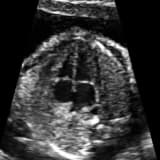

Bu grup hastalıkların çoğu anne karnındayken FETAL EKO ile tanınabilir ve doğum ve sonrası için uygun planlama yapılması sağlanır.